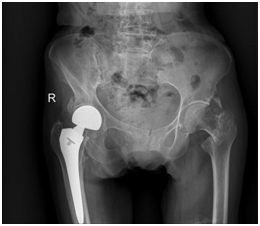

市一多学科团队携手百岁老人顺利越过“人生最后一次骨折”股骨粗隆间骨折是中老年人最常见的髋部骨折类型。这种骨折护理困难,无法翻身坐起,需长期卧床,所以褥疮、静脉血栓、肺炎等并发症较多,一年内的死亡率可达到30%—40%。因其高致残、致死率,常被称为“人生最后一次骨折”。对这类患者而言,及时、准确评估病情并尽早手术,是降...

三位九旬老人骨折后在滨医附院重新站立起来!齐鲁晚报齐鲁壹点 陈甜田 通讯员 刘栋 近日,滨州医学院附属医院创伤骨科在一周内连续为三位超高龄老人成功实施髋部骨折手术,展现了卓越的医疗技术和深厚的专业底蕴。髋部骨折,在老年人群中常被称为“人生最后一次骨折”,其危险性不言而喻。保守治疗虽为一种选择,但往往伴随...

潍坊市人民医院两位百岁髋骨折患者快速康复出院近日,在潍坊市人民医院创伤骨科与老年医学二科的共同努力下,2例百岁髋部骨折患者均康复出院。他们拉着孙学成主任的手,连连表示感谢,竖起了大拇指对李志玲主任表示赞扬。 髋部骨折被称为“人生最后一次骨折”,严重威胁老年人的生命和健康,潍坊市人民医院创伤骨科联合老年医...